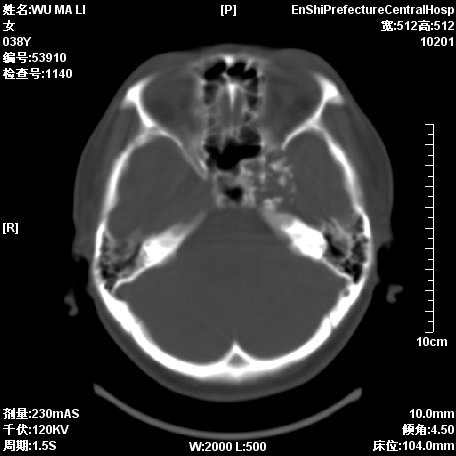

标题: CT11244:颅底病变,请教高手,已行MRI检查,随后发 [打印本页]

患者,38岁,因左侧偏盲月余求治.

脊索瘤?脑膜瘤?

图像不全啊,考虑脊索瘤可能性大.

考虑脊索瘤可能性大

考虑脊索瘤可能性

可考虑  脑膜瘤、脊索瘤、软骨瘤

支持脊索瘤诊断

脑膜瘤?脊索瘤?

考虑为:1)脊索瘤。2)软骨瘤?

支持脊索瘤

图像不全,考虑脊索瘤可能性大.

支持考虑:  脑膜瘤、脊索瘤、软骨瘤  。